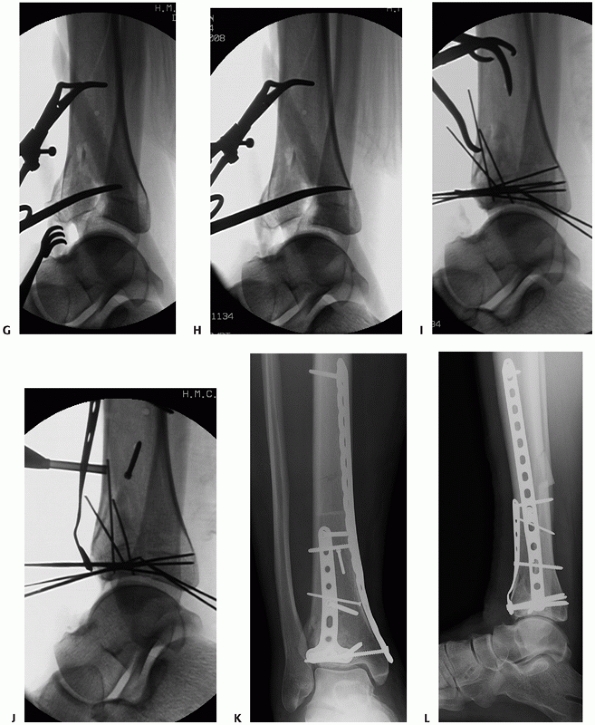

FIGURE 56-11 Illustration (A) and clinical example (B)

of the anterolateral exposure for a fracture of the tibial plafond. The incision is longitudinally oriented, in line with the fourth ray. Illustrated (C) and clinical (continues) |

FIGURE 56-11 (continued) (D)

example of the anterior compartment mobilized medially. A laterally based universal distractor is applied to facilitate visualization of the articular surface (E,F). Note the course of the superficial peroneal nerve. Anterolateral plating is performed (G,H), and the wound is closed with an Allgower-Donati suture technique (I). |